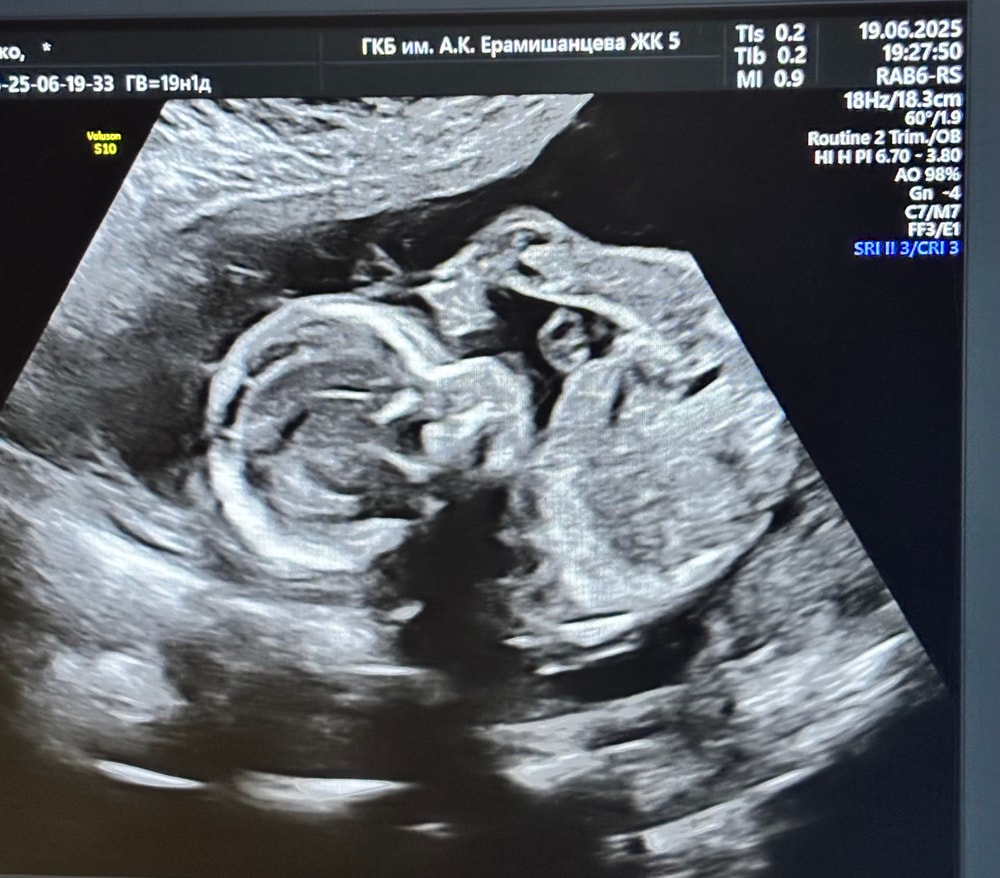

Пол в 19 недель

Пол малышаБыла вчера на 2 скрининге, с малышом все хорошо!))🥰

Кончено же спросила видно ли кто там, написали на листочке.💞 Хотим устроить гендер пати🎉, но переживаю мог ли врач ошибиться на таком сроке? Были ли у кого-то такие случаи?